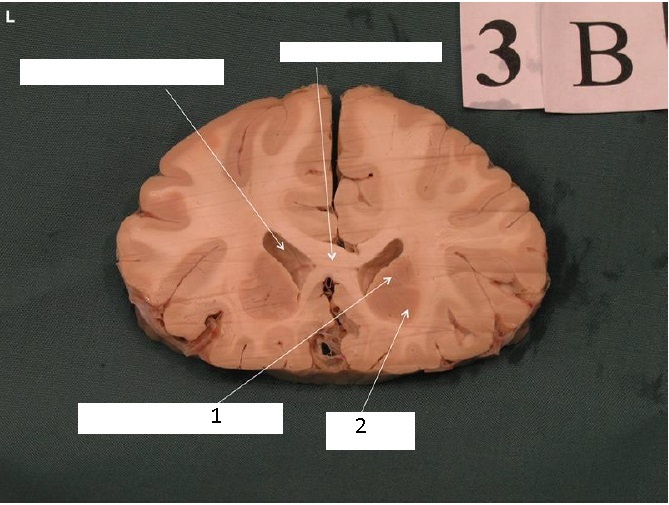

Identify 1

Head of Caudate Nucleus

Identify 2

Putamen